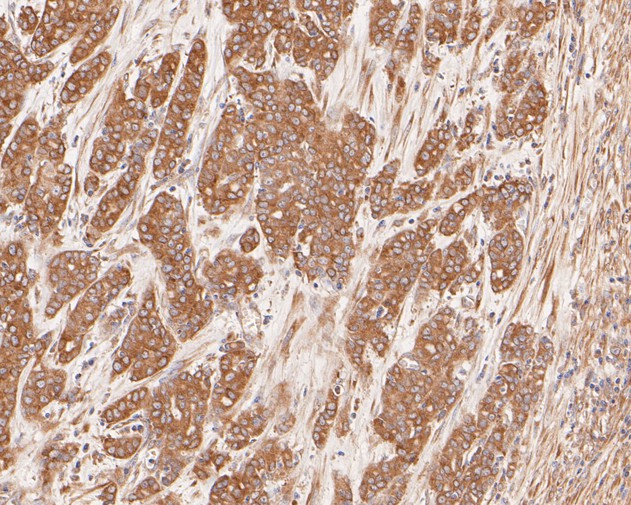

|   | Fig3: Immunohistochemical analysis of paraffin-embedded human colon carcinoma tissue using anti-Cytokeratin 20 antibody. The section was pre-treated using heat mediated antigen retrieval with Tris-EDTA buffer (pH 8.0-8.4) for 20 minutes.The tissues were blocked in 5% BSA for 30 minutes at room temperature, washed with ddH2O and PBS, and then probed with the primary antibody (EM1901-96, 1/500) for 30 minutes at room temperature. The detection was performed using an HRP conjugated compact polymer system. DAB was used as the chromogen. Tissues were counterstained with hematoxylin and mounted with DPX. |